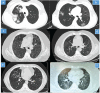

Results: At the three-month follow-up, 375 patients with post-COVID-19 syndrome were evaluated, and 262 patients were found to have post-COVID ILD. The most prevalent complaints were dyspnea (n = 238, 90.8%), exercise intolerance (n = 166, 63.4%), fatigue (n = 142, 54.2%), and cough (n = 136, 52%). The mean Medical Research Council dyspnea score was 2.1 ± 0.9, oxygen saturation was 92.2 ± 5.9%, and 6-minute walking distance was 360 ± 140 meters. The mean diffusing capacity of the lung for carbon monoxide was 58 ± 21, and the forced vital capacity was 70% ± 19%. Ground glass opacities and fibrotic bands were the most common findings on thoracic HRCT. Fibrosis-like lesions such as interlobular septal thickening and traction bronchiectasis were observed in 38.3% and 27.9% of the patients, respectively. No honeycomb cysts were observed. Active smoking [odds ratio (OR), 1.96; 95% confidence interval (CI), 1.44-2.67), intensive care unit admission during the acute phase (OR, 1.46; 95% CI, 1.1-1.95), need for high-flow nasal oxygen (OR, 1.55; 95% CI, 1.42-1.9) or non-invasive ventilation (OR, 1.31; 95% CI, 0.8-2.07), and elevated serum lactate dehydrogenase levels (OR, 1.23; 95% CI 1.18-1.28) were associated with the development of post-COVID ILD. At the 6-month follow-up, the respiratory symptoms and pulmonary functions had improved spontaneously without any specific treatment in 35 patients (13.4%). The radiological interstitial lesions had spontaneously regressed in 54 patients (20.6%).

Conclusion: The co-existence of respiratory symptoms, radiological parenchymal lesions, and pulmonary functional abnormalities which suggest a restrictive ventilatory defect should be defined as post-COVID-19 ILD. However, the term “fibrosis” should be used carefully. Active smoking, severe COVID-19, and elevated lactate dehydrogenase level are the main risk factors of this condition. These post-COVID functional and radiological changes could disappear over time in 20% of the patients.